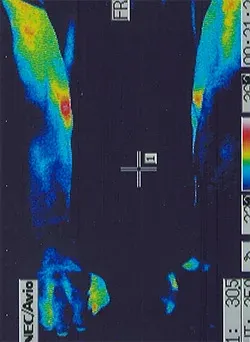

筋萎縮性側索硬化症|足の温度分布(治療前)

治療後

筋萎縮性側索硬化症|足の温度分布(治療後)

筋萎縮性側索硬化症は、進行する速度に個人差があります。足や背中の筋肉が低温になっている患者様は進行が早いですが、片手だけ低温の患者様は進行が遅い印象を受けます。鍼治療で筋肉の温度が上がるほど治療効果が高まる感じがしますが、どの程度の治療効果が上がるかは、個人差があります。